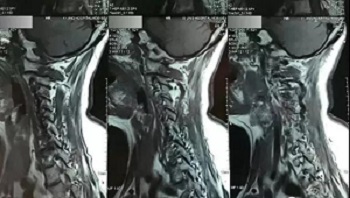

十一、将分区的磁共振图像,按顺序进行拍摄,即可获取如下比较有价值的清晰图片

(区域7)

(区域8)